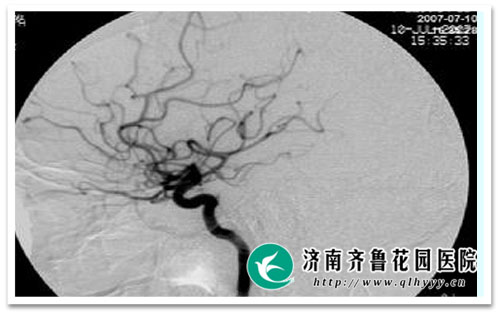

脑血管造影